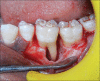

Periodontal regeneration is defined as the reproduction or reconstitution of a lost or injured part to restore the architecture and function of the periodontium. The ultimate goal of periodontal therapy is to regenerate the lost periodontal tissues caused by periodontitis. The most positive outcome of periodontal regenerative procedures in intra bony defect has been achieved with bone grafts. For complete regeneration, delivery of growth factors in a local environment holds a great deal in adjunct to bone grafts. Platelet rich fibrin (PRF) is considered as second generation platelet concentrate, consisting of viable platelets, releasing various growth factors. Hence, this case report aims to investigate the clinical and radiological (bone fill) effectiveness of autologous PRF along with the use of alloplastic bone mineral in the treatment of intra bony defects.